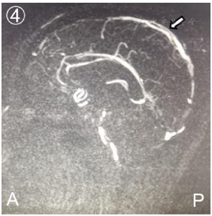

头颅CT:左侧额顶叶及右侧颞叶血肿,头颅MRV:颅内静脉窦血栓形成。

患者,男性,22岁,主因"头痛伴发作性抽搐、右侧麻木无力2 d"于2020年11月13日入院。入院6周前因工作原因进入高原地区(海拔5400m)执行任务,出现间断头部隐痛,考虑急性高原反应,给予常规对症处理后症状减轻。入院2 d前休息状态下出现头痛加剧伴右侧肢体麻木,否认意识障碍、恶心呕吐等症状,数小时后晕倒伴全身抽搐,发作数次,当地卫生院初诊为"癫痫",具体治疗不详,后转送至我院急救部。2020年11月13日头颅电子计算机断层扫描(Computed Tomography, CT)提示:左侧额顶叶及右侧颞叶血肿(图1);头颅核磁共振静脉成像(Magnetic Resonance Venography, MRV)提示:右侧颈静脉、乙状静脉窦、横窦及上矢状窦内信号不均(图2),考虑血栓形成。入院体检:体温36.9℃,脉搏84次/min,呼吸18次/min,血压136/75mmHg;意识嗜睡,反应迟钝,双侧瞳孔等大等圆、直径约2mm,反射灵敏,双侧额纹对称,右侧鼻唇沟变迁,伸舌偏右,颈阻阴性,右上肢肌力0级,右下肢肌力1级,左侧肢体肌力5级,四肢肌张力正常,生理反射正常,右侧巴氏征阳性。